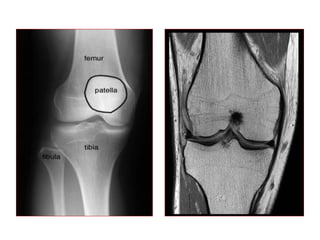

RM X RADIOGRAFIA

TC X RM